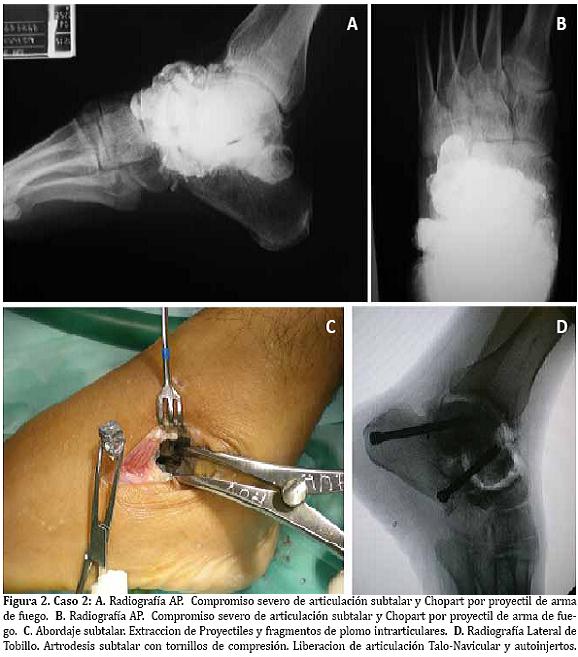

Gota gruesa (-). VIH: (-). Valorado por Medicina Interna y Neurología con impresión diagnostica de: Mielopatía Viral, secuelas de Guillain-Barré. Radiografías con presencia de múltiples fragmentos de plomo en la columna lateral del pie con destrucción parcial del Cuboides.(Figura 1A)

Posterior a la terapia quelante, el paciente fue llevado a cirugía para extracción de los proyectiles y reconstrucción del medio pié. (Figuras 1B-C).

Paciente masculino de 38 anos, cuadro de 3 años de evolución de dolor abdominal paroxístico, emesis postprandial y pérdida de peso. Manejo medico con mejoría parcial del cuadro. Progresa con exacerbación de los síntomas, comportamiento bizarro, agresividad y convulsiones. Antecedente hace 15 anos de herida por arma de fuego en pie. Tabaquismo y alcoholismo hasta la embriaguez. Al exámen físico con disminución de la fuerza muscular de predominio niveles medulares C5 - T1. Hiporeflexia aquiliana. El cuadro hemático y frotis de sangre periférica evidencian anemia microcítica hipocrómica. Niveles de Plomo: 90.3 µg/dl. Radiografía de pie con evidencia de múltiples fragmentos metálicos a nivel de articulaciones del mediopié. Artrosis de articulaciones Calcáneo-cuboidea , Talo-navicular y subtalar (Figura 2A).

Se hace el diagnóstico de Saturnismo, inicio de terapia Quelante con EDTA (50 mg/Kg/día) por 7 días. Es llevado a cirugía para extracción de los proyectiles alojados en pie y artrodesis del retropié. (Figuras 2B-D).